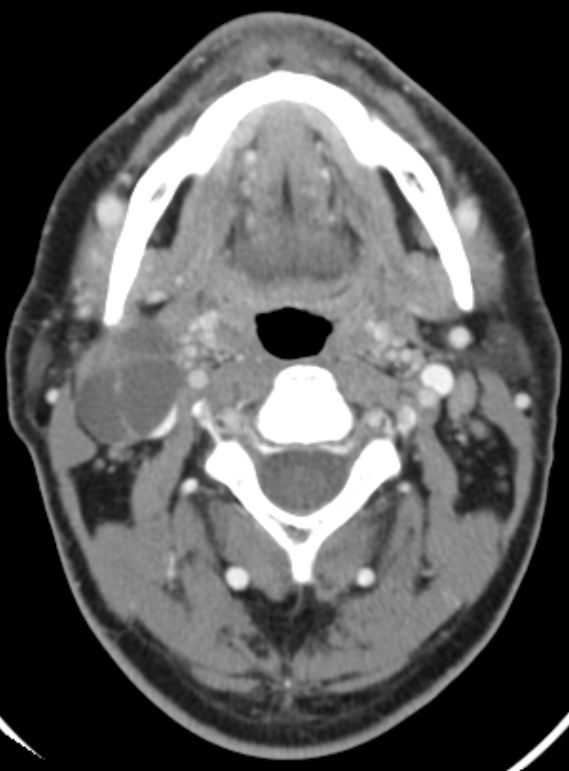

Tonsillentumor asymptomatisch. Das große Lymphknotenpaket am Unterkieferwinkel war aufgefallen.